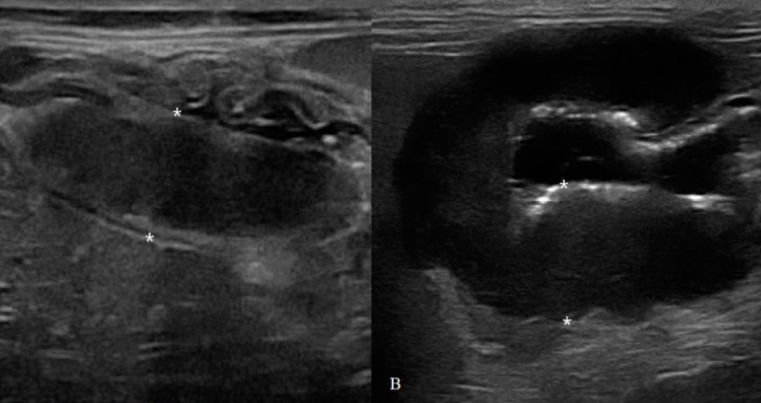

고양이 침윤성장질환과 장종양의 구분 방법

high grade의 종양성 변화가 아닌 low grade의 종양인경우 결론적으로 구분점은 없다고 보아야 한다.

low grade에서는 종양이어도 층간 구조 소실이 보이지 않기 때문에 함부로 종양이다, 종양이 아니다를 말해서는 안된다.

high grade라면 그냥 초음파만 봐도 악해 보이니 바로 감별이 가능하긴 하다